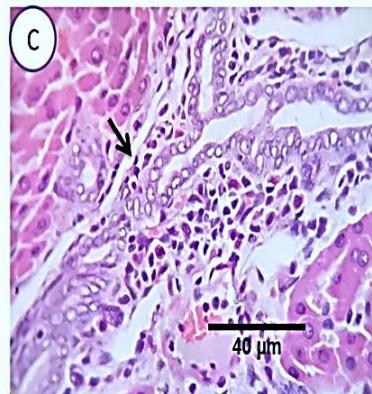

Fig. 4: Photo-micrograph from liver, group (4), showing, portal biliary proliferation (A, yellow arrow, B, black arrow), congestions of portal blood vessels(A, black arrow), round cell infiltration and interstitial lymphocytic and macrophages aggregations replacing previous necrotic patches (B, blue arrow). Scale bars 120, 40, 40 um.

Liver: Sections from liver of this group denoted moderate portal biliary proliferation, congestion of portal blood vessels, round cell infiltration, multifocal interstitial lymphocytic and macrophages aggregations replacing previous necrotic patches beside degenerative changes in a few hepatocytes. (Fig.10)

### d) Group 4 (Ginger protection followed by methomyl administration)